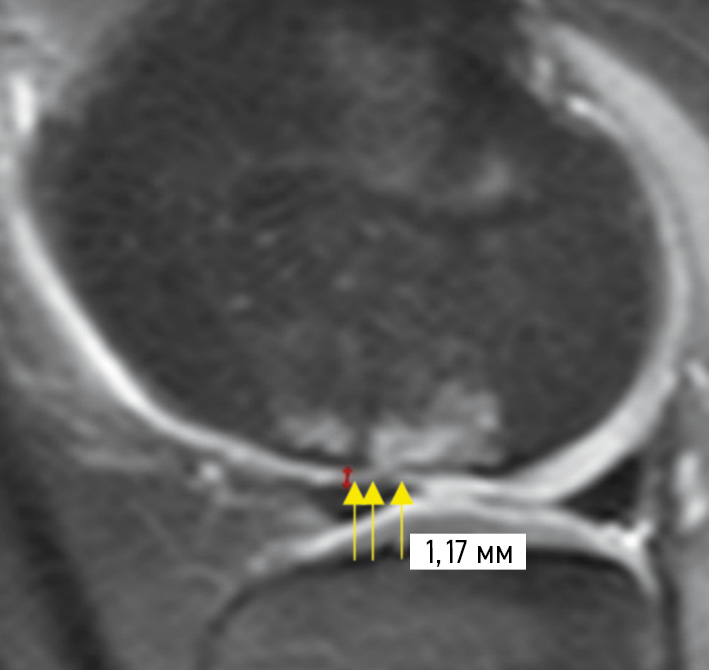

In Figure 4, thinning and hypointensity of the signal from the articular cartilage in the OD lesion are observed. The MRI shows a grade III cartilage damage, according to ICRS. The score was 30 points.

Fig. 4. Magnetic resonance imaging of the knee joint (sagittal PD-FS image) of a child with an osteochondritis dissecans lesion. Thinning and hypointensity of the signal from the articular cartilage in the OD lesion are observed. The magnetic resonance picture shows a grade III cartilage damage, according to ICRS